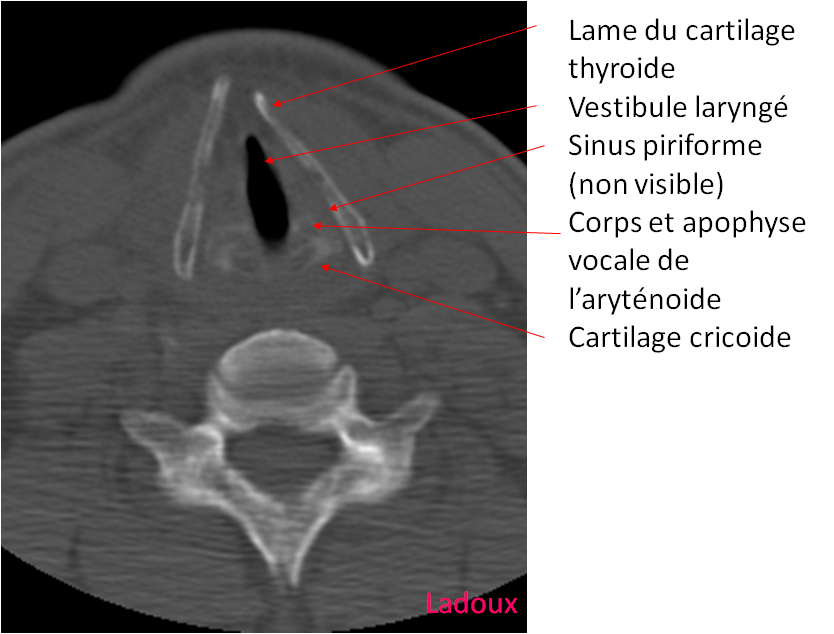

Larynx,

Absence de syndrome de masse de la filière pharyngo laryngée décelé.

Déplissement satisfaisant des sinus piriformes après manœuvre de Vasalva.